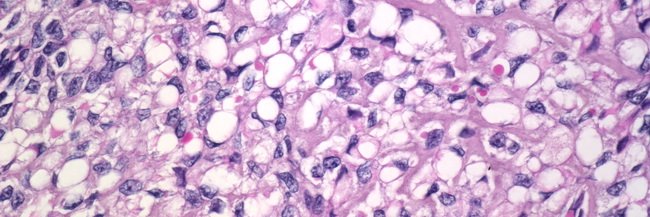

Our work detailing the relationship between leiomyoma with bizarre nuclei and leiomyosarcoma is out now through the Journal of Pathology (open access!).